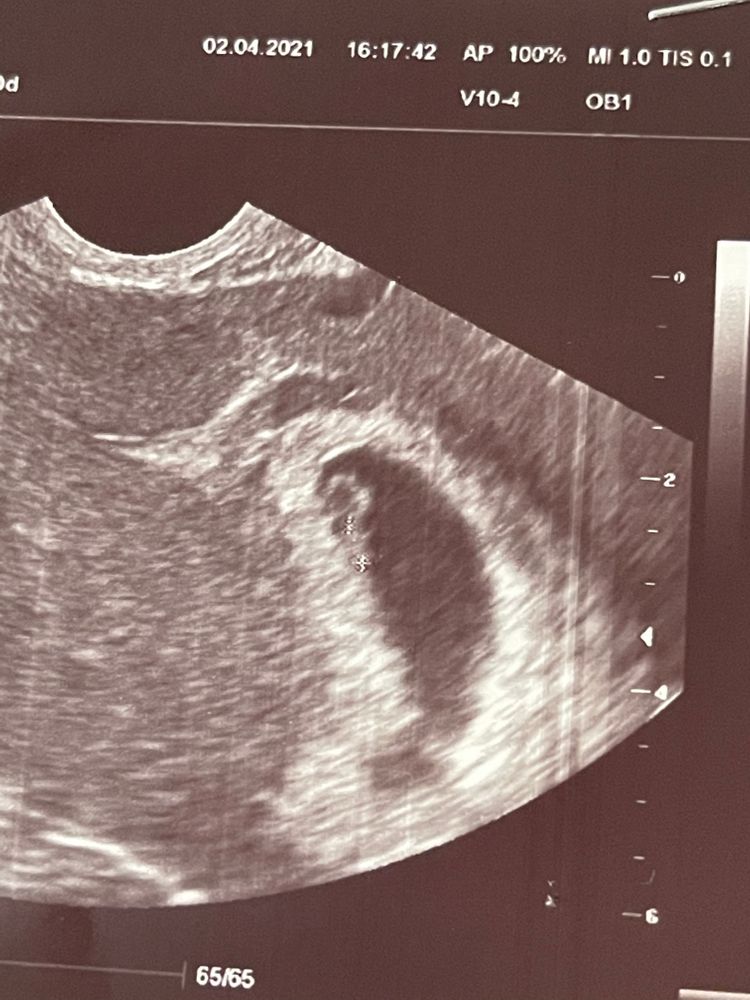

Моя бусинка появилась 😍сердечко бьется. Прикрепилась высоко. Размеры на 6-7 недель. Сказали все хорошо. Но есть киста на правом яичнике довольна большая. Правый яичник у меня частично удалён после лапароскопии. Он уже недели 1,5 переодически колет. Судя по размерам киста даже больше левого яичника.

Узи в 7 недель.